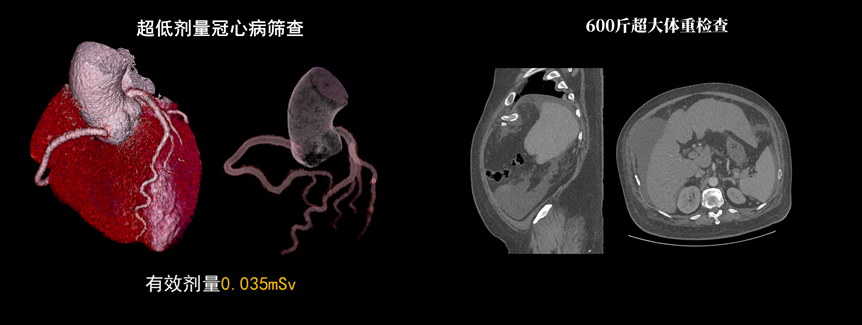

該設(shè)備除具備普通CT的功能外,還具備速度快、精度高、智能化、高效能、微劑量、大孔徑等優(yōu)勢。16厘米Z軸探測器、23毫秒時(shí)間分辨率,聯(lián)影天河640CT讓冠脈CTA檢查擁有“不選擇”的權(quán)利。搭載的一站式聯(lián)合掃描技術(shù),輔以便捷高效的后處理功能,AI精準(zhǔn)血管分割,自動(dòng)預(yù)處理加載,逐支血管觀察,全時(shí)提效,可實(shí)現(xiàn)一次注射造影劑獲取多部位CTA、CTP和4D動(dòng)態(tài)圖像,不僅可以助力腦卒中解決方案,還可助力腦血管畸形、腦動(dòng)脈瘤等其他腦血管病的結(jié)構(gòu)和功能評(píng)估。

液態(tài)金屬軸承球管,陽極直冷技術(shù),提供30MHU球管熱容量,可高通量連續(xù)掃描。AI劑量調(diào)制、迭代重建等復(fù)合劑量控制方案,為體檢患者提供優(yōu)化劑量掃查。82cm大孔徑,讓大體型患者檢查更加舒適。

天河640CT的寬體探測器單圈掃描即可覆蓋全心臟,搭配快速機(jī)架轉(zhuǎn)速和獨(dú)家AI冠脈追焦技術(shù),可實(shí)現(xiàn)單心動(dòng)周期內(nèi)無限心率、無限心律的冠脈成像,對(duì)于嚴(yán)重心律不齊、房顫、房撲,超高心率等情況,天河640CT都能在單心動(dòng)周期內(nèi)獲得優(yōu)質(zhì)圖像。

通過3D視圖可任意旋轉(zhuǎn)觀看血管全貌,AI秒級(jí)實(shí)時(shí)計(jì)算重建血管,可實(shí)現(xiàn)多維輔診包含:板塊定性定量分析、狹窄評(píng)估、心肌橋檢出、支架檢出、鈣化積分,全程AI關(guān)注心血管健康。